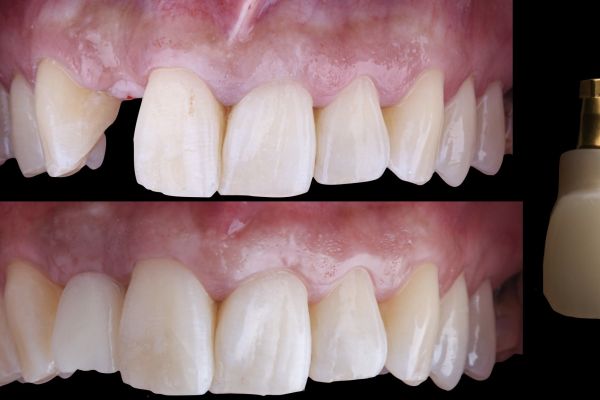

Manejo quirúrgico y restaurador de un implante en área estética y evaluación volumétrica tras un injerto de tejido conectivo desepitelizado. Descripción de un caso clínico

El reto del abordaje quirúrgico en la rehabilitación sobre un implante unitario en un caso de alto requerimiento estético del sector anterior. Descripción a propósito de un caso

The challenge of the surgical approach in the rehabilitation of an anterior sector unitary implant in a case of high aesthetic requirements; case report